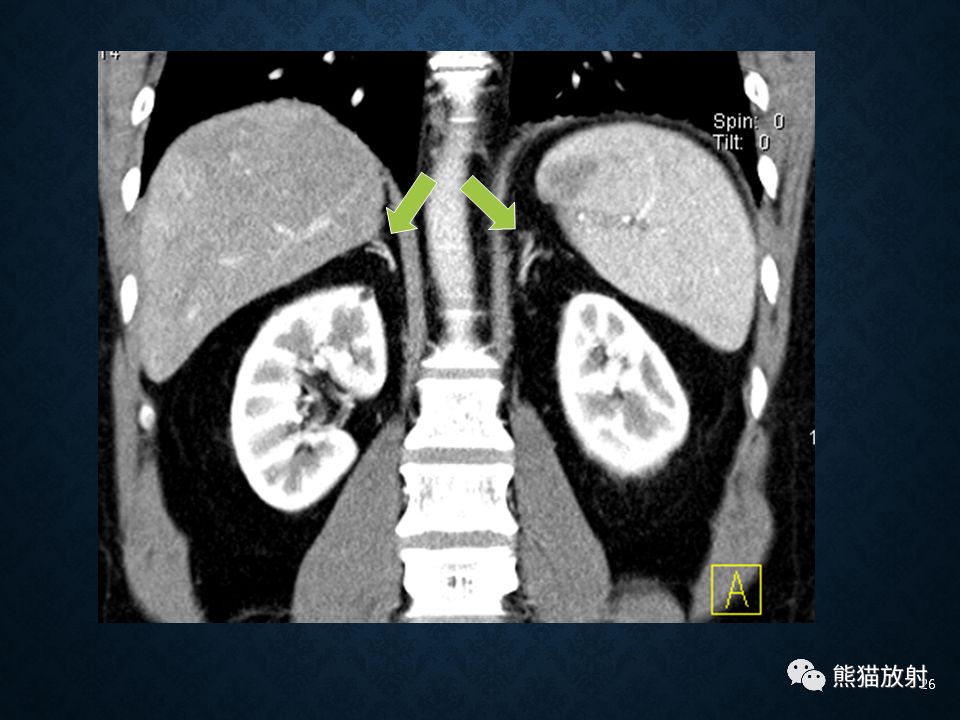

肾上腺常见肿瘤影像诊断

>先天性肾上腺增生:双侧肾上腺腺体显著弥漫性增大,程度常明显超过 Cushing综合征的皮质增生